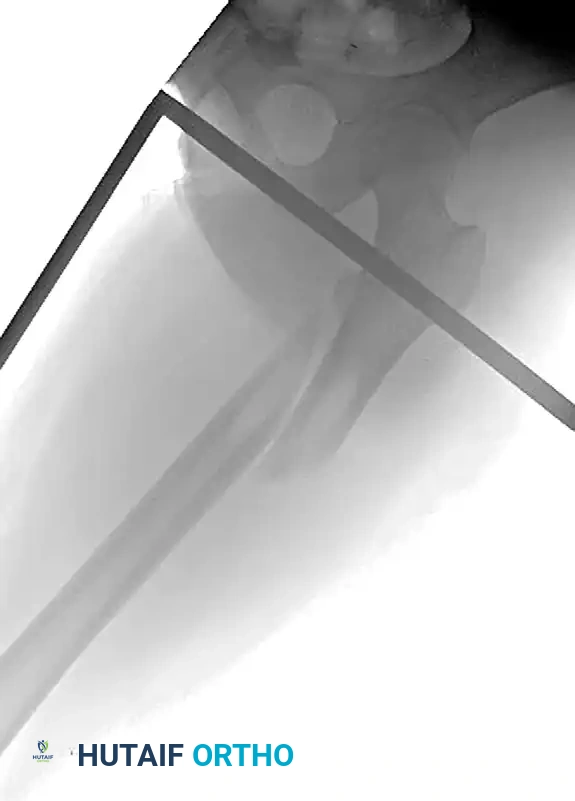

The Femur

- Distal Femur: The safe zone is strictly lateral or anterior. Medial pins risk injury to the superficial femoral artery and vein in the adductor canal.

- Proximal Femur: Pins are typically placed laterally, aiming toward the lesser trochanter, avoiding the femoral neurovascular bundle anteriorly and the sciatic nerve posteriorly.